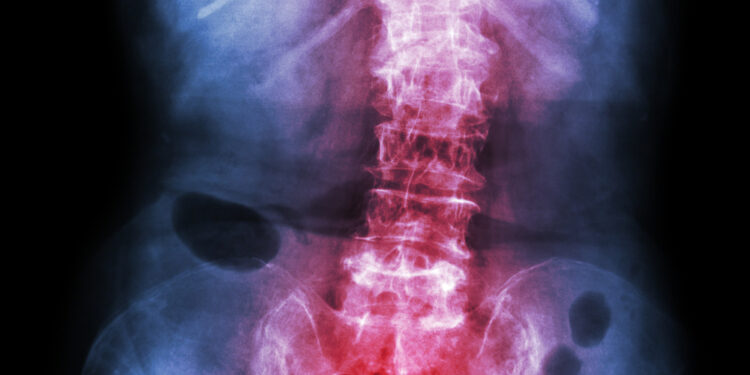

Norint geriau suvaldyti ankilozinį spondilitą, svarbu kuo daugiau apie šią ligą išmokti. Suprasdami savo būklę bei įvairius jos simptomus, galite sustiprinti savo savikontrolę ir pagerinti kasdienio gyvenimo kokybę.

Nors pats terminas gali atrodyti painus, ankilozinis spondilitas – kompleksinė ir daugeliui individualiai pasireiškianti būklė. Kiekvienam ji gali sukelti skirtingus simptomus. Kruopščiai renkantis informaciją, bendraujant su medikais ar konsultuojantis su specialistais, galima pasirūpinti savimi daug efektyviau. Informacijos gausa leidžia lengviau susidoroti su kasdieniais sunkumais, būti aktyviu savo gydymo procese ir gerinti savijautą.